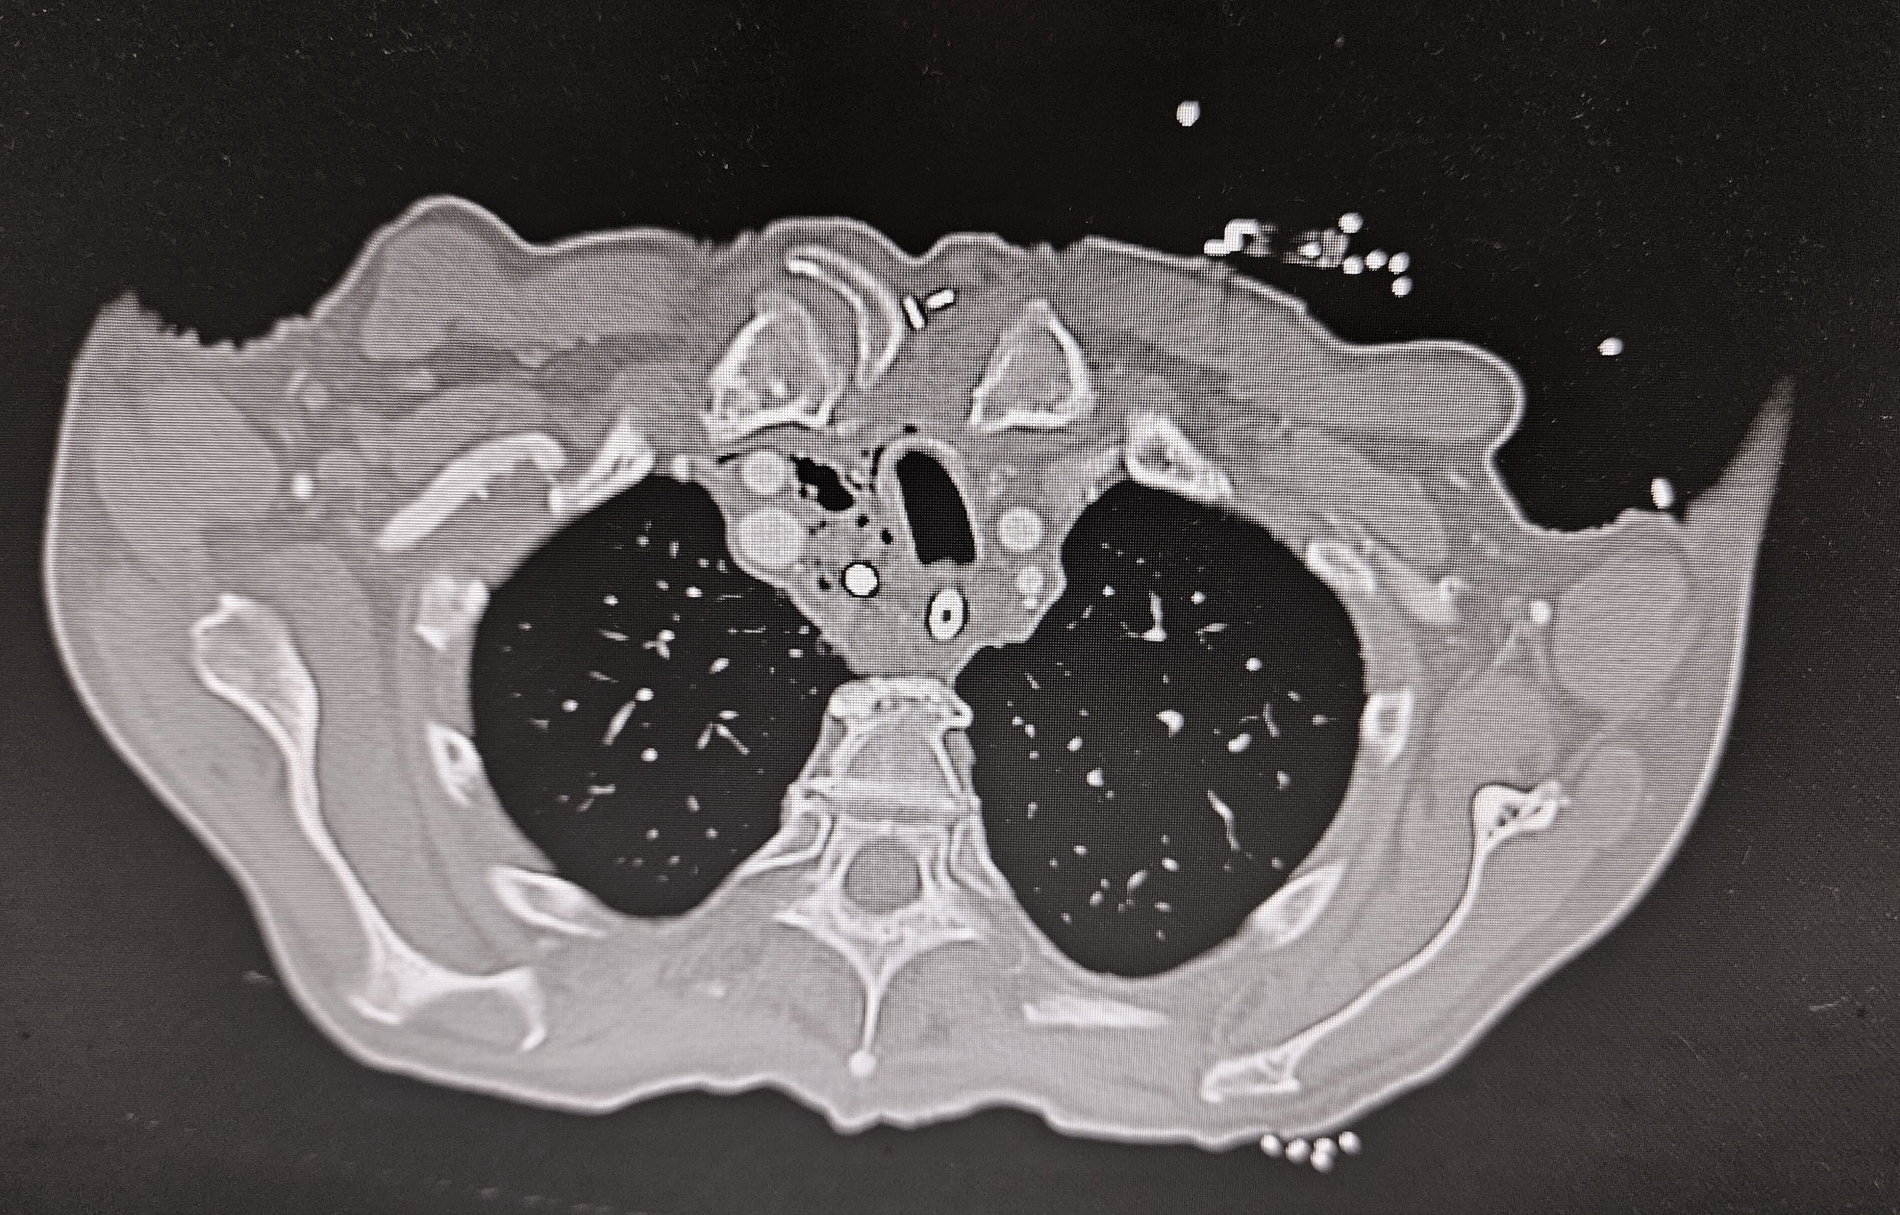

Während der Ösophagoskopie kam es zu einer traumatischen Perforation der Speiseröhre bei etwa 22 cm ab Zahnreihe. Zudem wurde während der Untersuchung ein anscheinend stark gelockertes dentales Implantat unbemerkt entfernt und nach aboral disloziert, bis es durch die simultan entstandene Perforation des Ösophagus in das Mediastinum verlagert wurde. Da eine intraoperative Verletzung des Ösophagus nicht ausgeschlossen werden konnte, wurde unmittelbar postoperativ eine Computertomografie von Hals und Thorax veranlasst. Diese zeigte rechtsseitig paraösophageal abgrenzbare Luft im Mediastinum, beginnend vom Kieferwinkel bis kurz kranial des Aortenbogens (Abbildung 1) sowie einen metalldichten Fremdkörper im Bereich des oberen Mediastinums (Abbildungen 2 und 3).